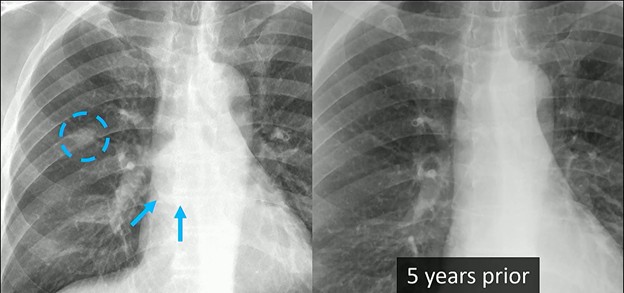

Here, we do see a nodule in the right lung. And it certainly looks discreet. Could it be an abnormality within the overlapping rib? Perhaps. Could it be something on the patient’s skin? Maybe, but probably not.

Finding associated abnormalities can turn a “maybe” into a “must-scan,” and in this case from Dr. Henry’s ARRS Web Lecture, a closer look reveals a huge subcarinal lymph node.

Clinical Context: The diagnostic weight of these findings increases significantly when combined with the patient’s history. This individual had a remote history of epithelioid angiosarcoma. While there was no known metastatic disease at the time, the combination of a new nodule and significant lymphadenopathy is highly concerning.